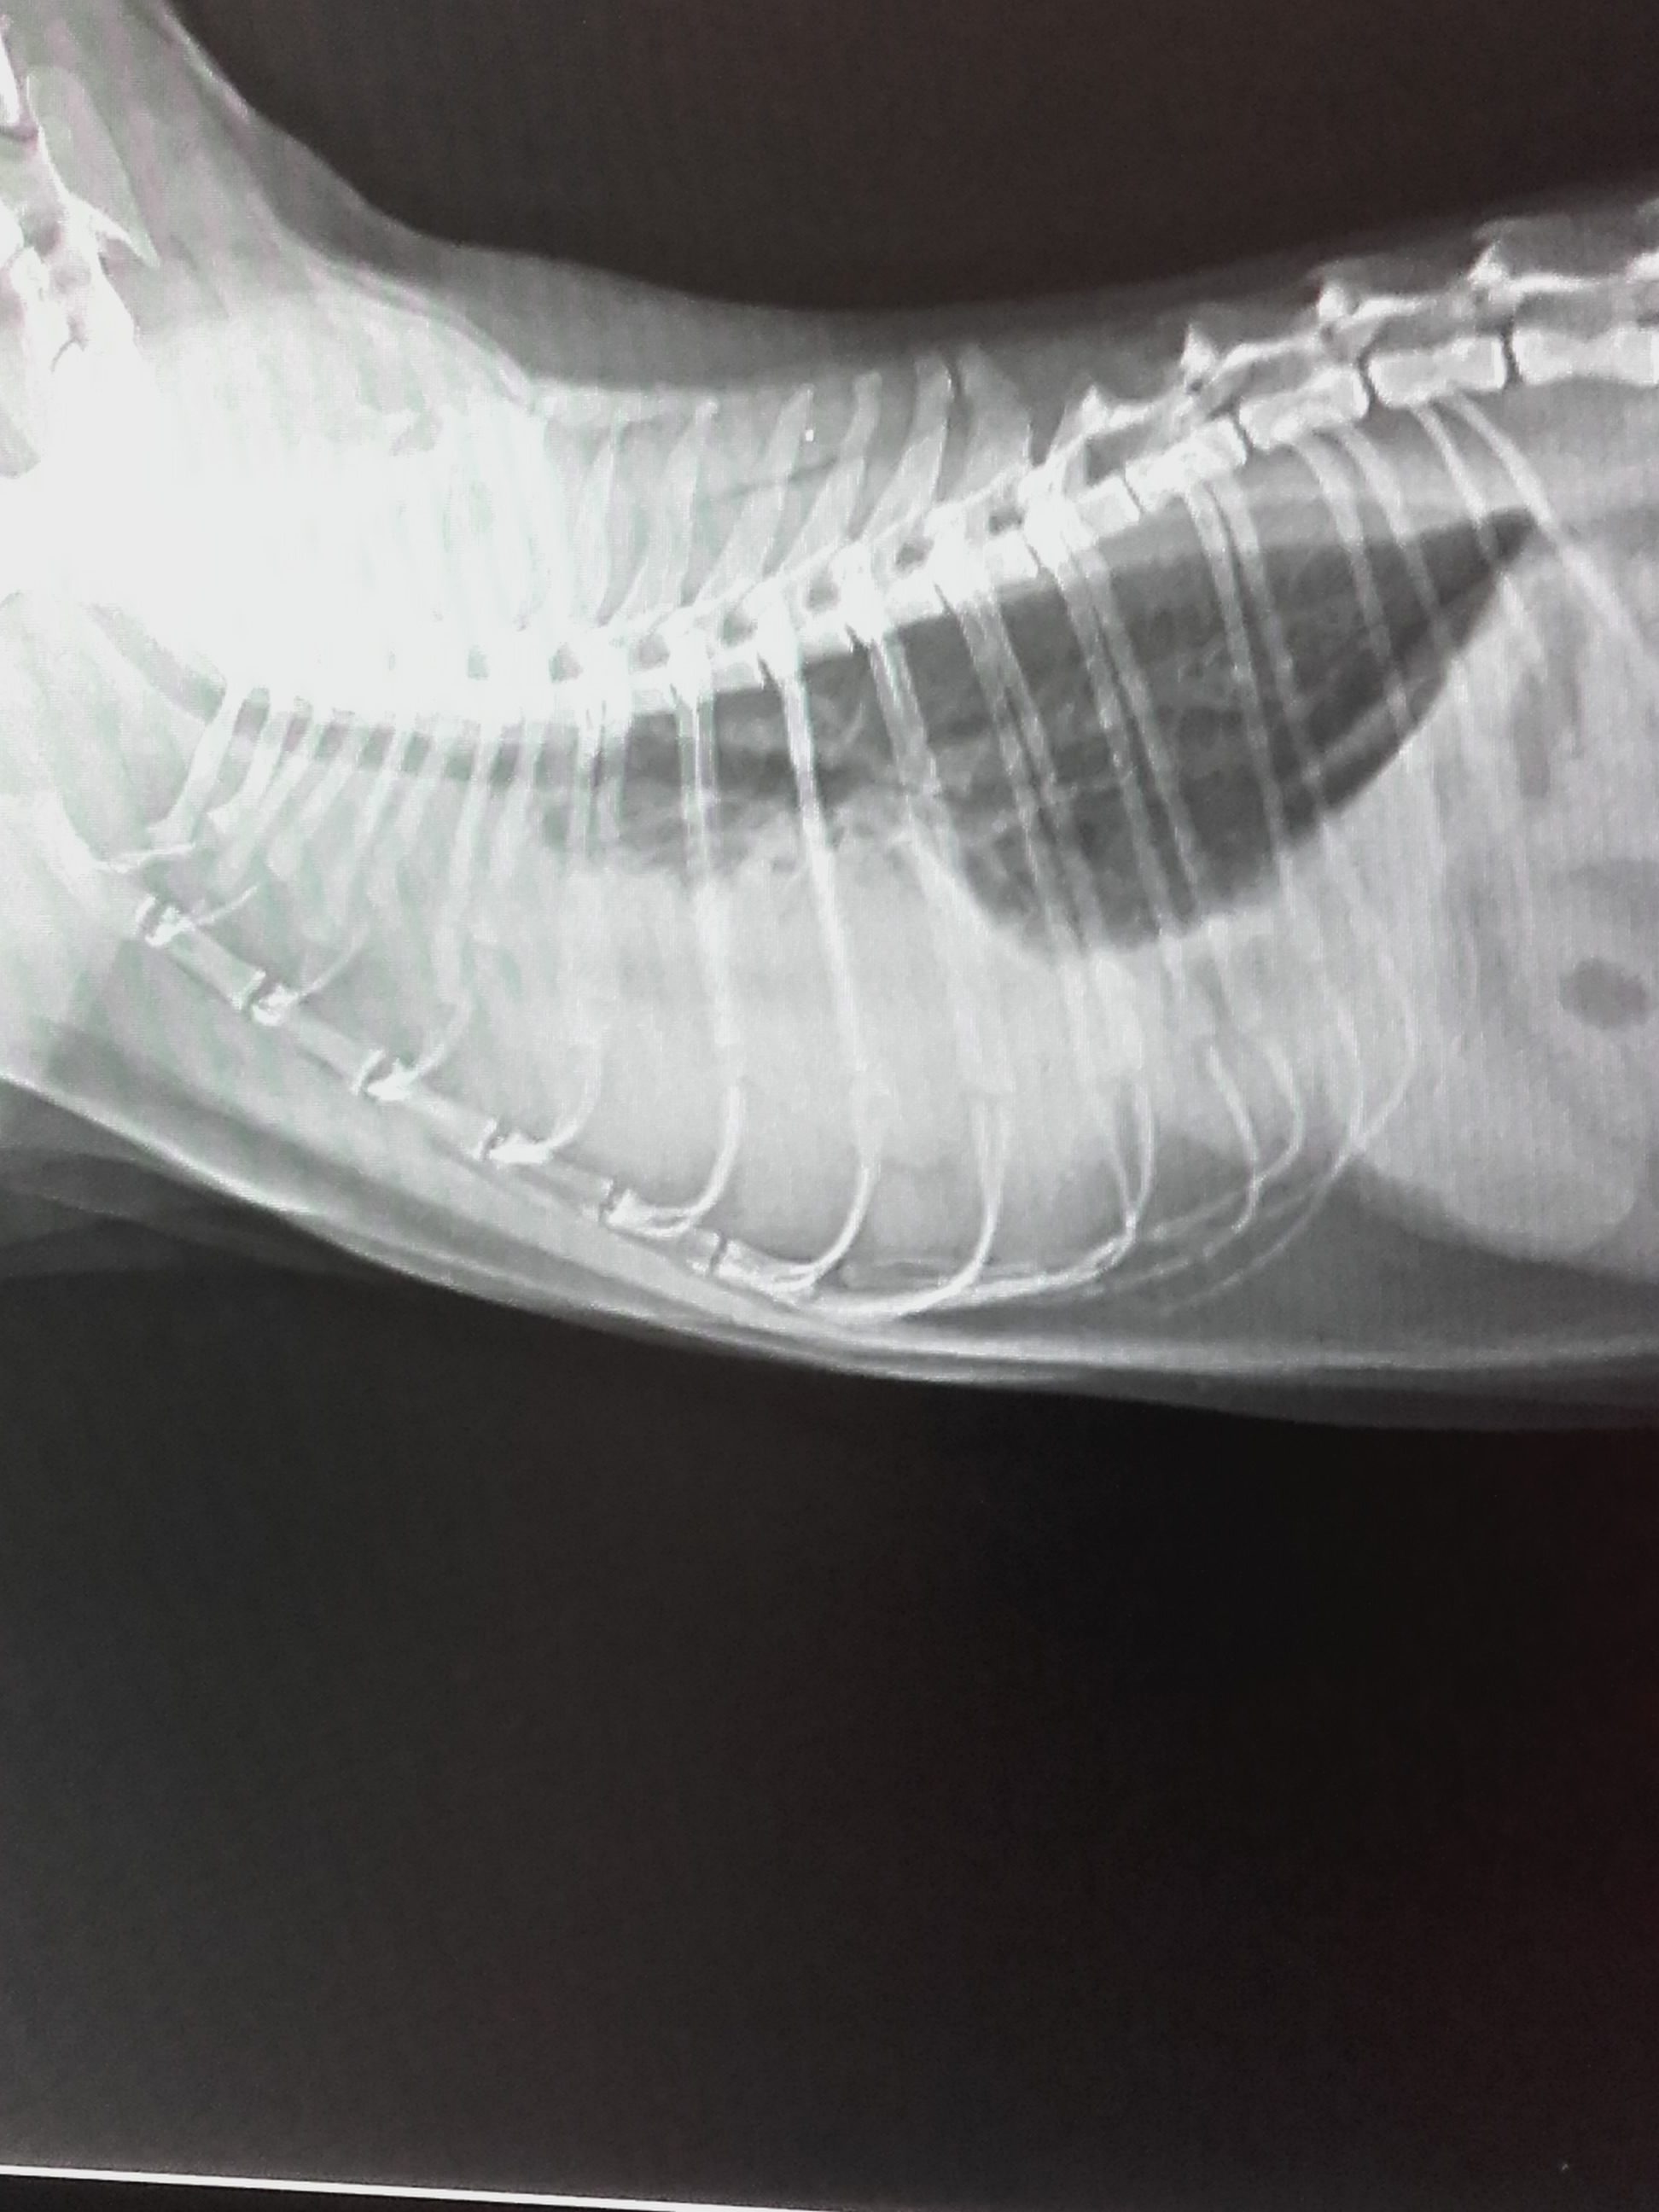

- Thoraxerguss (Brustkorberguss) bei einer Katze.

- Das war dann im Thorax (Brustkorb) drinnen.